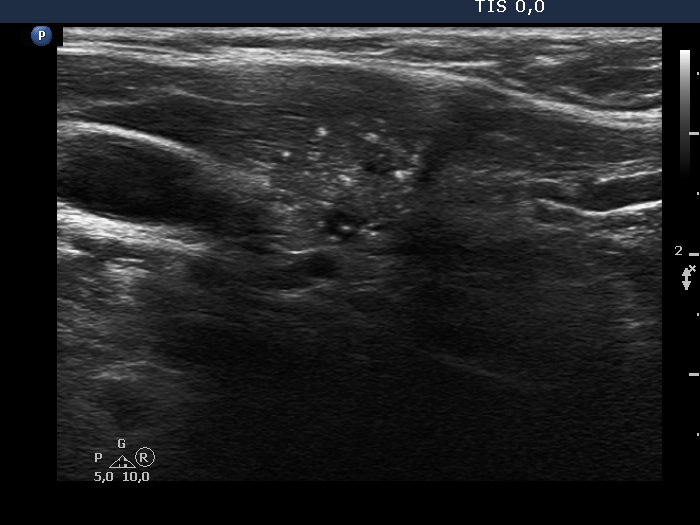

Ultrasonography. The thyroid was echonormal. There was a dominantly hypoechoic nodule in the left lobe. The nodule had both microcalcifications and macrocalcification and was avascular.